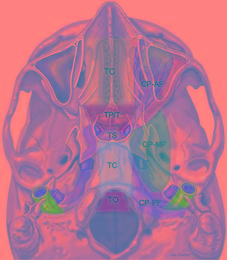

| Abstract | Background Spinal cerebrospinal fluid (CSF) leakage is frequently encountered clinically after lumbar puncture or spontaneous events. Although some patients recover without treatment or after intensive hydration, some require an epidural blood patch (EBP). The risks of nonresponsive hydration remain unknown. Therefore, we identified the risk factors for patients with spinal CSF leakage nonresponsive to hydration. Methods We retrospectively reviewed patients diagnosed with spinal CSF leakage between January 2010 and March 2021. Clinical data, including patient age, sex, etiology, and radiological indications in magnetic resonance imaging, were compared between patients who were responsive and non-responsive to hydration. Results Of the 74 patients with spinal CSF leakage, 25 were responsive to hydration and 49 required EBP. Patients who were nonresponsive to hydration were older (39.27 vs. 34.32 years, P = 0.01), had a higher percentage of spontaneous intracranial hypotension (93.88% vs. 68.00%, P = 0.005), had more spinal CSF leakage (12.04 vs. 8.04, P = 0.01), and had a higher percentage of dural sinus engorgement (81.63% vs. 60.00%, P = 0.044). Spontaneous intracranial hypotension (odds ratio [OR]: 4.63; 95% confidence interval [CI]: 1.00-21.38) and having ≥9 spinal CSF leakages (OR: 3.29; 95% CI: 1.08-10.01), as indicated by magnetic resonance myelography, are considered risk factors for noneffective hydration. Conclusions Patients with spinal CSF leakage who have spontaneous intracranial hypotension and those with ≥9 spinal CSF leakages are considered at risk for noneffective hydration. EBP should be considered early in these patients. |